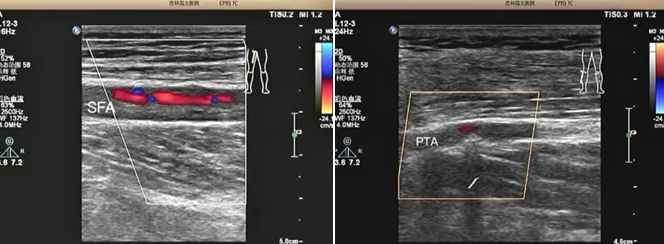

該患者是一位老年男性,因 “雙小腿麻木、發(fā)涼 2 個月” 前來我院就診。超聲科為其進行下肢動靜脈彩超檢查時,精準(zhǔn)發(fā)現(xiàn)其股淺動脈及脛后動脈存在重度狹窄至閉塞的情況。超聲檢查憑借其無創(chuàng)、便捷的獨特優(yōu)勢,在第一時間就為臨床治療提供了準(zhǔn)確無誤的診斷依據(jù),為后續(xù)治療方案的制定奠定了堅實基礎(chǔ)。

超聲檢查以其無創(chuàng)、便捷、可重復(fù)的顯著優(yōu)勢,在此次診療過程中發(fā)揮了重要作用,清晰地顯示了患者下肢動脈的病變情況:1、準(zhǔn)確判斷病變部位:精準(zhǔn)定位到股淺動脈及脛后動脈。2、明確病變程度:確定為重度狹窄至閉塞。3、評估側(cè)支循環(huán)建立情況:為治療方案的制定提供了關(guān)鍵參考。